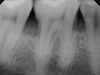

2. Fig 2. Periapical radiograph showing presence of distal bone loss and calculus.

Figure 2